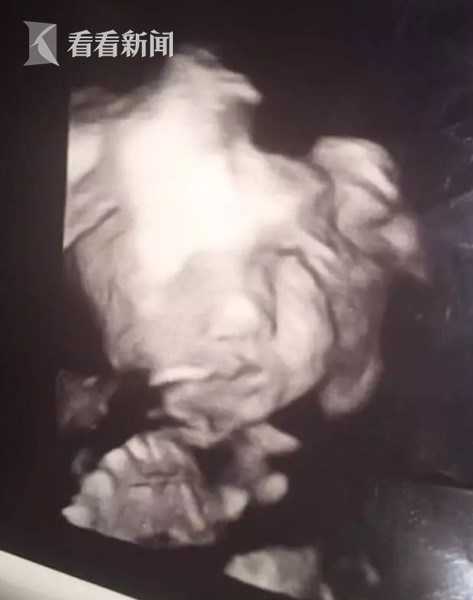

近日,在美国弗吉尼亚州首府里士满,一位名叫凯琳顿的妈妈怀孕24周,前往医院接受产检,超音波画面中显示女性胎儿眨着大眼睛,咧嘴露出诡异笑容,凯琳顿被当场吓坏。据医生称,胎儿的一切情况均正常,无需担心。凯琳顿把照片上传到社交媒体上,立即引发网友广泛关注,有网友称是假照片,也有网友认为,现在医学检测技术发达,拍到胎儿高清照片实属正常。

综合外媒报道,现年17岁的凯琳顿在怀孕24周时,到医院进行性别扫描,得知宝宝是女孩以后,却意外被孩子的表情吓坏。据她发布在社交媒体上贴文描述,一般婴儿都会躲避镜头,但女儿却眨着一双圆滚滚的大眼睛,咧嘴大笑。

凯琳顿还透露:“超音波画面上,宝宝的脸一开始很正常,护士确认是女生,当医生把镜头转回孩子脸上,她就这样看着我。”

报道称,当时躺在黑暗房间里看超音波,凯琳顿的确被突如其来的鬼脸吓了一大跳,可是得知一切正常后非常安心。